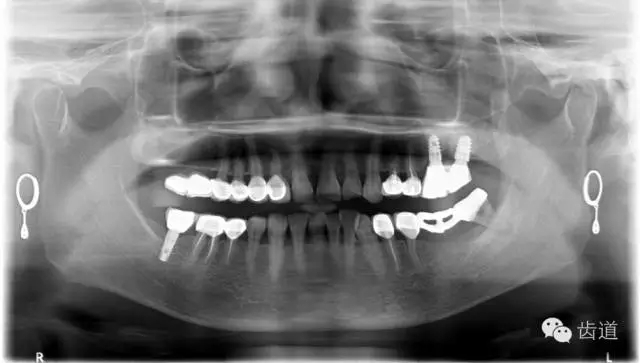

4、 全景片

1、治療前

2、治療后